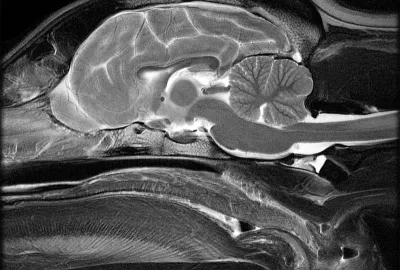

MRI (magnetická rezonance)

MRI je nejlepší pro zobrazení mozku a nervového systému – ukáže například nádory, záněty mozku a mozkových obalů, krvácení, cévní příhody nebo problémy s míchou v oblasti krční páteře. Poskytuje nejdetailnější obraz měkkých tkání, ale vyšetření trvá déle a je dražší než CT.